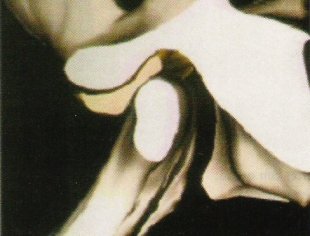

• Luxación. Cuando el disco aparece desplazado en los tres cortes. Se hace estudio con la boca abierta y con la boca cerrada para ver si se recaptura o no. Tendremos dos posibilidades:

1. Luxación con reducción. Se recaptura el disco al abrir la boca. Será una lesión de menor gravedad. Aparece un chasquido al recapturarse, o una desviación mandibular.

2. Luxación sin reducción. No se recaptura el disco al abrir la boca. Será una lesión de mayor gravedad. Es el último estadío de todo este proceso crónico y degenerativo. El disco está luxado siempre e igual que en los casos anteriores, ocupando normalmente una posición anterior respecto al cóndilo. No hay chasquidos, suele haber dolor y limitación a la apertura.